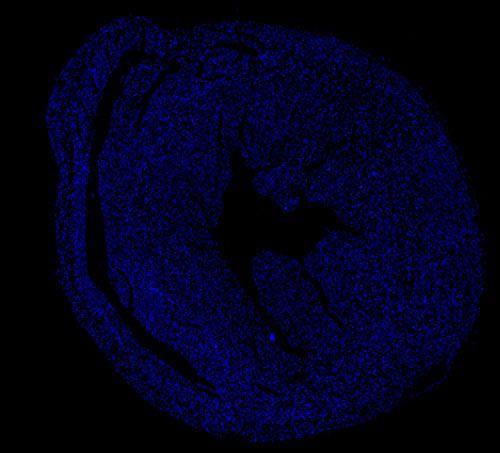

DAPI染色-小鼠心臟